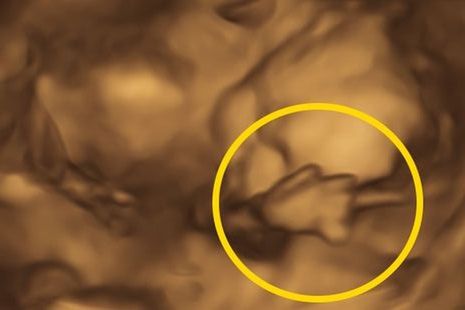

Kiedy Ang Slater z Pensylwanii była w 25. tygodniu ciąży poszła na badanie USG 3D. Kobieta miała nadzieję, że wreszcie zobaczy twarz swojej córeczki. Nie spodziewała się jednak, że zobaczy o wiele więcej.

Dziewczynka podczas badania wykonała gest, który zarówno jej rodzicom, jak i lekarzowi wykonującemu zdjęcie jednoznacznie dał do zrozumienia, że nie chce być podglądana. Pokazała im bowiem środkowy palec - skierowany wprost do sondy ultrasonograficznej.